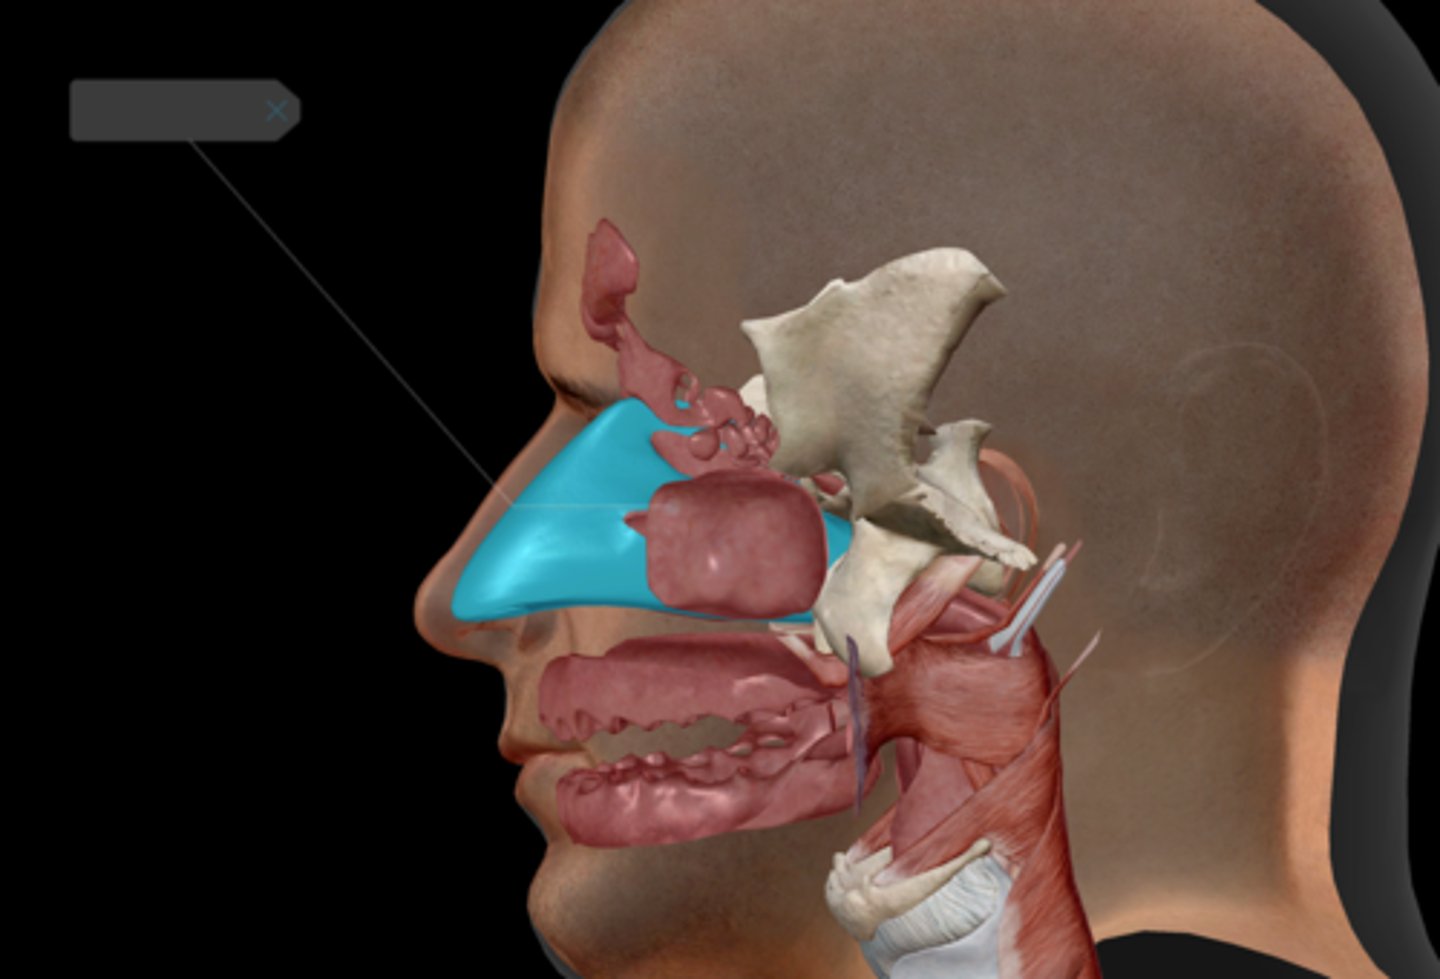

Nasal cavity

Nasopharynx